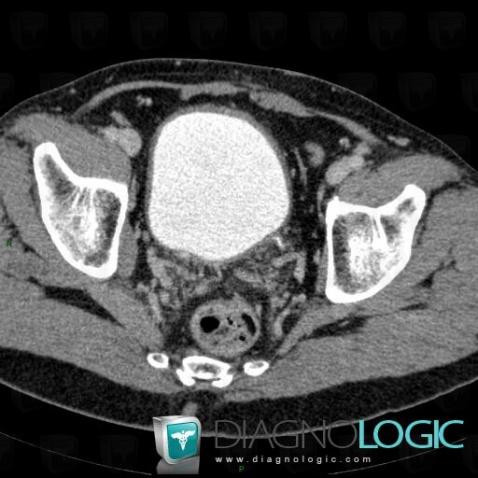

Chronic bladder outlet obstruction, Urinary bladder, CT

- Diagnosis Chronic bladder outlet obstruction, Location(s) Urinary bladder, with gamuts Thickening of bladder wall

Benign prostatic hyperplasia, Prostate, CT

- Diagnosis Benign prostatic hyperplasia, Location(s) Prostate, with gamuts